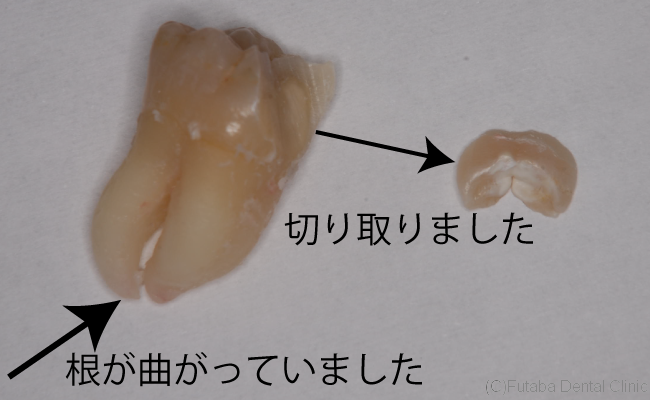

こんな状態では、普通には歯は抜けません。

ぶつかっている部分を切り取ってから、歯を抜きます。

無事に抜けてよかったです。

術中痛みもなく、神経も傷つけることなく、抜けました。

今回の手術時間は、5分でした。

常に、手術時間は短くするよう心がけています。

手術時間の短縮は予後にかなり影響します。

術後の疼痛、腫れなど、できるだけ侵襲の少ない手術が必要です。